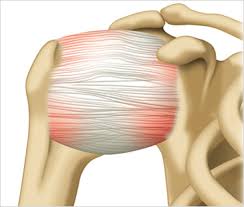

회전근개는 어깨 관절을 감싸는 네 개의 힘줄로 구성되어 있습니다. 이 근육들은 팔을 움직이고 관절을 고정시키는 데 핵심 역할을 하며, 작은 손상에도 큰 불편을 초래할 수 있습니다. 이 부위가 반복적인 자극이나 외부 충격으로 인해 찢어지면 어깨 회전근개 파열 원인에 해당하는 상태가 되는 거예요.